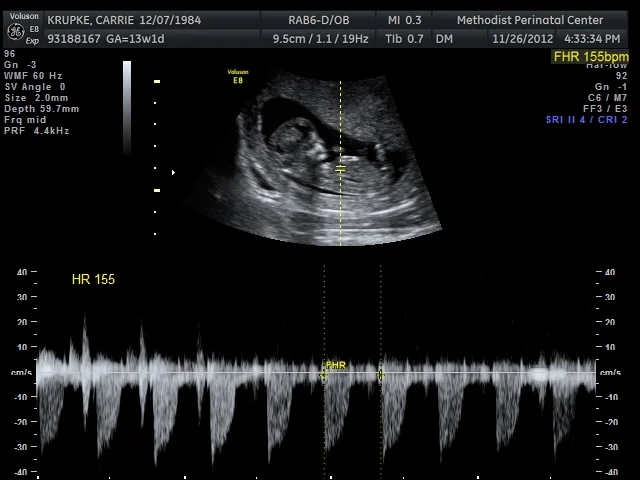

*that we were able to see and hear the heartbeat and get an audio recording. (Gerard thinks I have a train growing inside me. And judging by this photo, our child is already wielding a sword.)